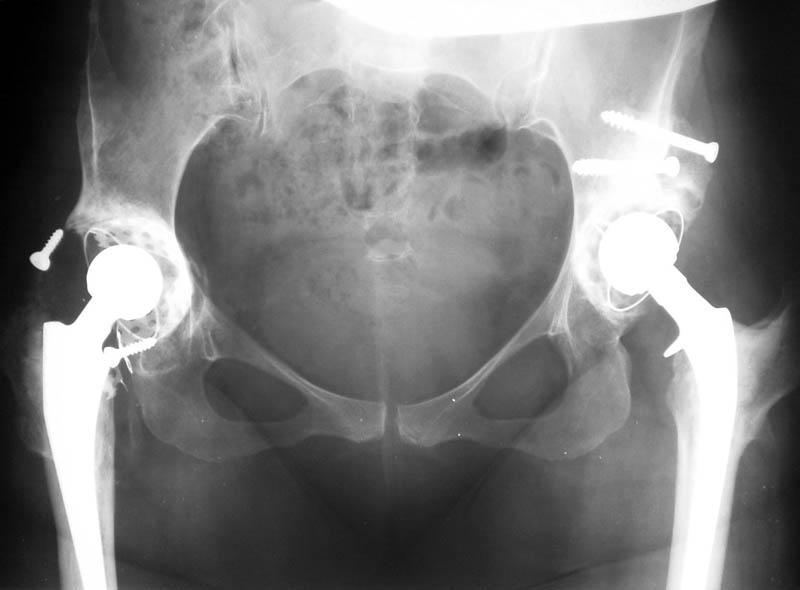

Вывих чашки

Мужчина, 38 лет. Двусторонний диспластический коксартрз, кифосколиоз. Правый сустав прооперирован 12.12.00, левый - в апреле 2003 г. Справа вывихнулась <чашка>.

Предполагается заменить <чашку>, наростив крышу <тутопластом>? Возможно ли использовать бесцементную <чашку>? Мнения? Заранее благодарю! С уважением, А.В.Владзимирский